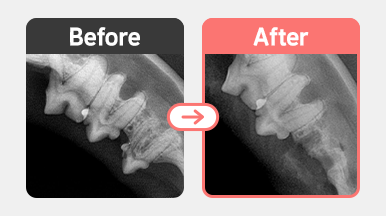

치과용 X-ray 검사 결과 PD4 M0 치주염과 함께 치아흡수성병변(FORL)이 확인되었습니다.

이 중 일부는 치근 흡수가 진행된 Type 2 양상으로 Crown Amputation(치관 절제술)이 적합했으며,

나머지 병변은 치근 손상 및 치조골 변화가 심해 외과적 발치가 필요한 상태였습니다.